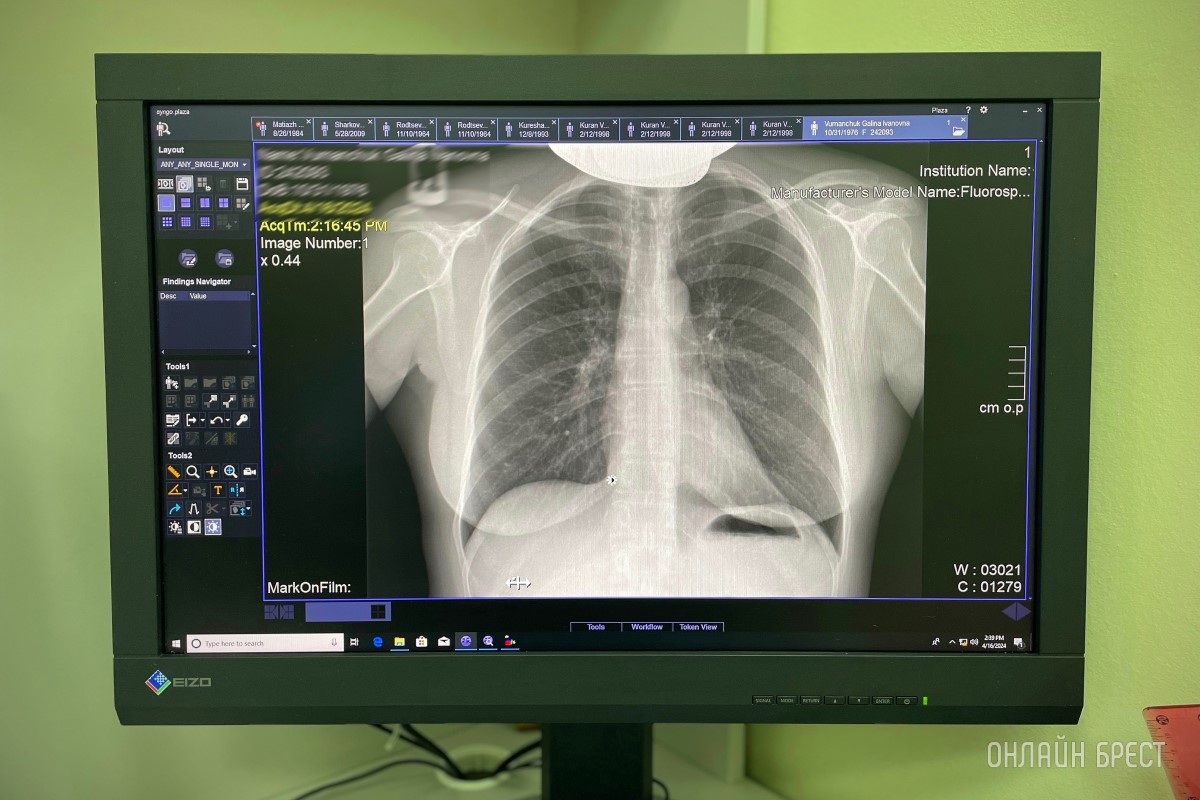

На базе нового корпуса по адресу ул. Ленина, 66-1 полноценно ведет работу отделение лучевой диагностики, которое оснащено современным оборудованием, позволяющим обследовать пациента в полном объёме от классического рентгеновского исследования до магнитно-резонансной томографии.

Рентгенодиагностические кабинеты оснащены современным высокоточным европейским оборудованием, что гарантирует высокое качество изображения и максимально точные результаты при низкой лучевой нагрузке.

Стоимость рентгеновских исследований снизилось более чем на 30%! Без очереди выполняем цифровую рентгенографию:

• Органов грудной клетки.